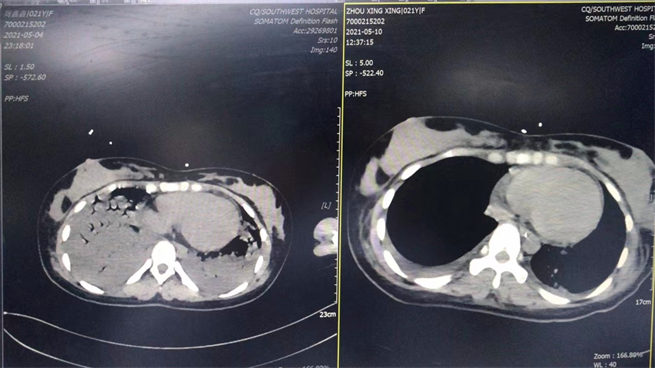

5月4日是剛轉進科時和5月10日是撤ecom后做的CT對比圖。西南醫院供圖!

當地醫院全力救治但病情仍持續加重,小嫣被迅速轉入了西南醫院心內科。入院時,小嫣已經意識喪失、嚴重休克,需要氣管插管呼吸機維持呼吸、血壓也需要去甲腎上腺素維持,心肌酶譜提示心肌鈣蛋白飆升數十倍、心臟超聲發現心臟收縮泵功能嚴重下降。初步判斷考慮為:暴發性心肌炎、心力衰竭、心源性休克!

小嫣就是因為暴發性心肌炎、全心衰竭,出現了血壓和呼吸難以維持、無尿、意識喪失,反復的室早、室顫等癥狀。如果沒有得到積極有效的治療,她將會有生命危險。